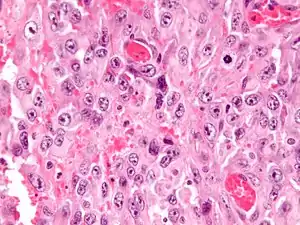

Histologically, epithelioid sarcoma forms nodules with central necrosis surrounded by bland, polygonal cells with eosinophilic cytoplasm and peripheral spindling.[3] Epithelioid sarcomas typically express vimentin, cytokeratins, epithelial membrane antigen, and CD34, whereas they are usually negative for S100, desmin, and FLI1 (FLI-1).[3] They typically stain positive for CA125.[4]

High mag.